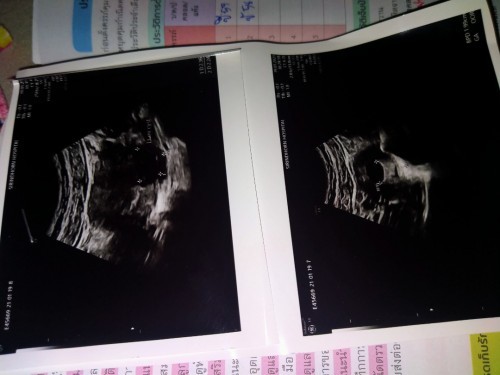

ซาวเจอถุงตั้งครรภ์ ค่ะ

ตอนนี้ซาวเจอแต่ถุงตั้งครรภ์ใครเคยเป็นบ้างค่ะ หมอนัดซาววันที่2กพ. อีกครั้งค่ะ #ขอคำแนะนำหน่อยค่ะ #ขอบคุณสำหรับคำตอบค่ะ #ขอบคุณล่วงหน้านะคะ

เจอถุงตั้งครรภ์ก่อนค่ะ ตัวน้องยังเล็กมากอยู่ค่ะ ☺คุณหมอนัดครั้งต่อไปมีโอกาสเห็นมากขึ้นค่ะ